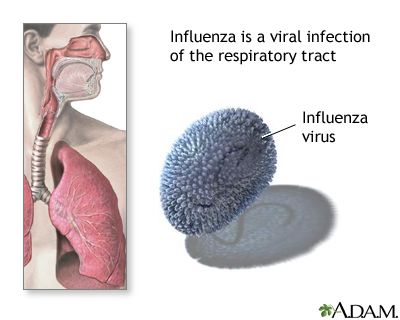

Influenza

Influenza is also known as the flu. It is caused by the influenza virus. The virus spreads easily from person to person. The flu causes a sore throat, fever and chills, headache, muscle ache, cough, and fatigue. Influenza is responsible for over 200,000 hospitalizations a year in the US and results in thousands of deaths.

Pneumonia is a major serious complication of the flu. It nearly always occurs in high-risk people such as the very young or very old and pregnant women. People who are hospitalized or whose immune systems are weakened are also at high risk of complications.

Influenza, also known as the flu, is caused by a virus.

There are 3 types of the influenza virus that can infect humans:

- Type A is the most widespread. It can affect both animals and humans. In humans, it can cause severe illness. Influenza A is the cause of all the worldwide outbreaks (pandemics) of the flu. In recent years, subtypes of influenza A that were only known to infect animals, such as the avian (bird) flu viruses, have begun to infect humans. The new subtype A virus, 2009 H1N1, which was discovered in 2009, causes severe illness.

- Type B infects only humans and is also responsible for seasonal epidemics. Young children are mostly affected by type B. Flu caused by this strain tends to be milder than that caused by influenza A.

- Type C also infects humans but is not thought to cause epidemics. Like type B, it mainly affects young children and the illness is mild.

Each influenza virus has different subtypes or strains. The seasonal flu vaccines work by protecting against those strains which experts think will be the most common for that season.